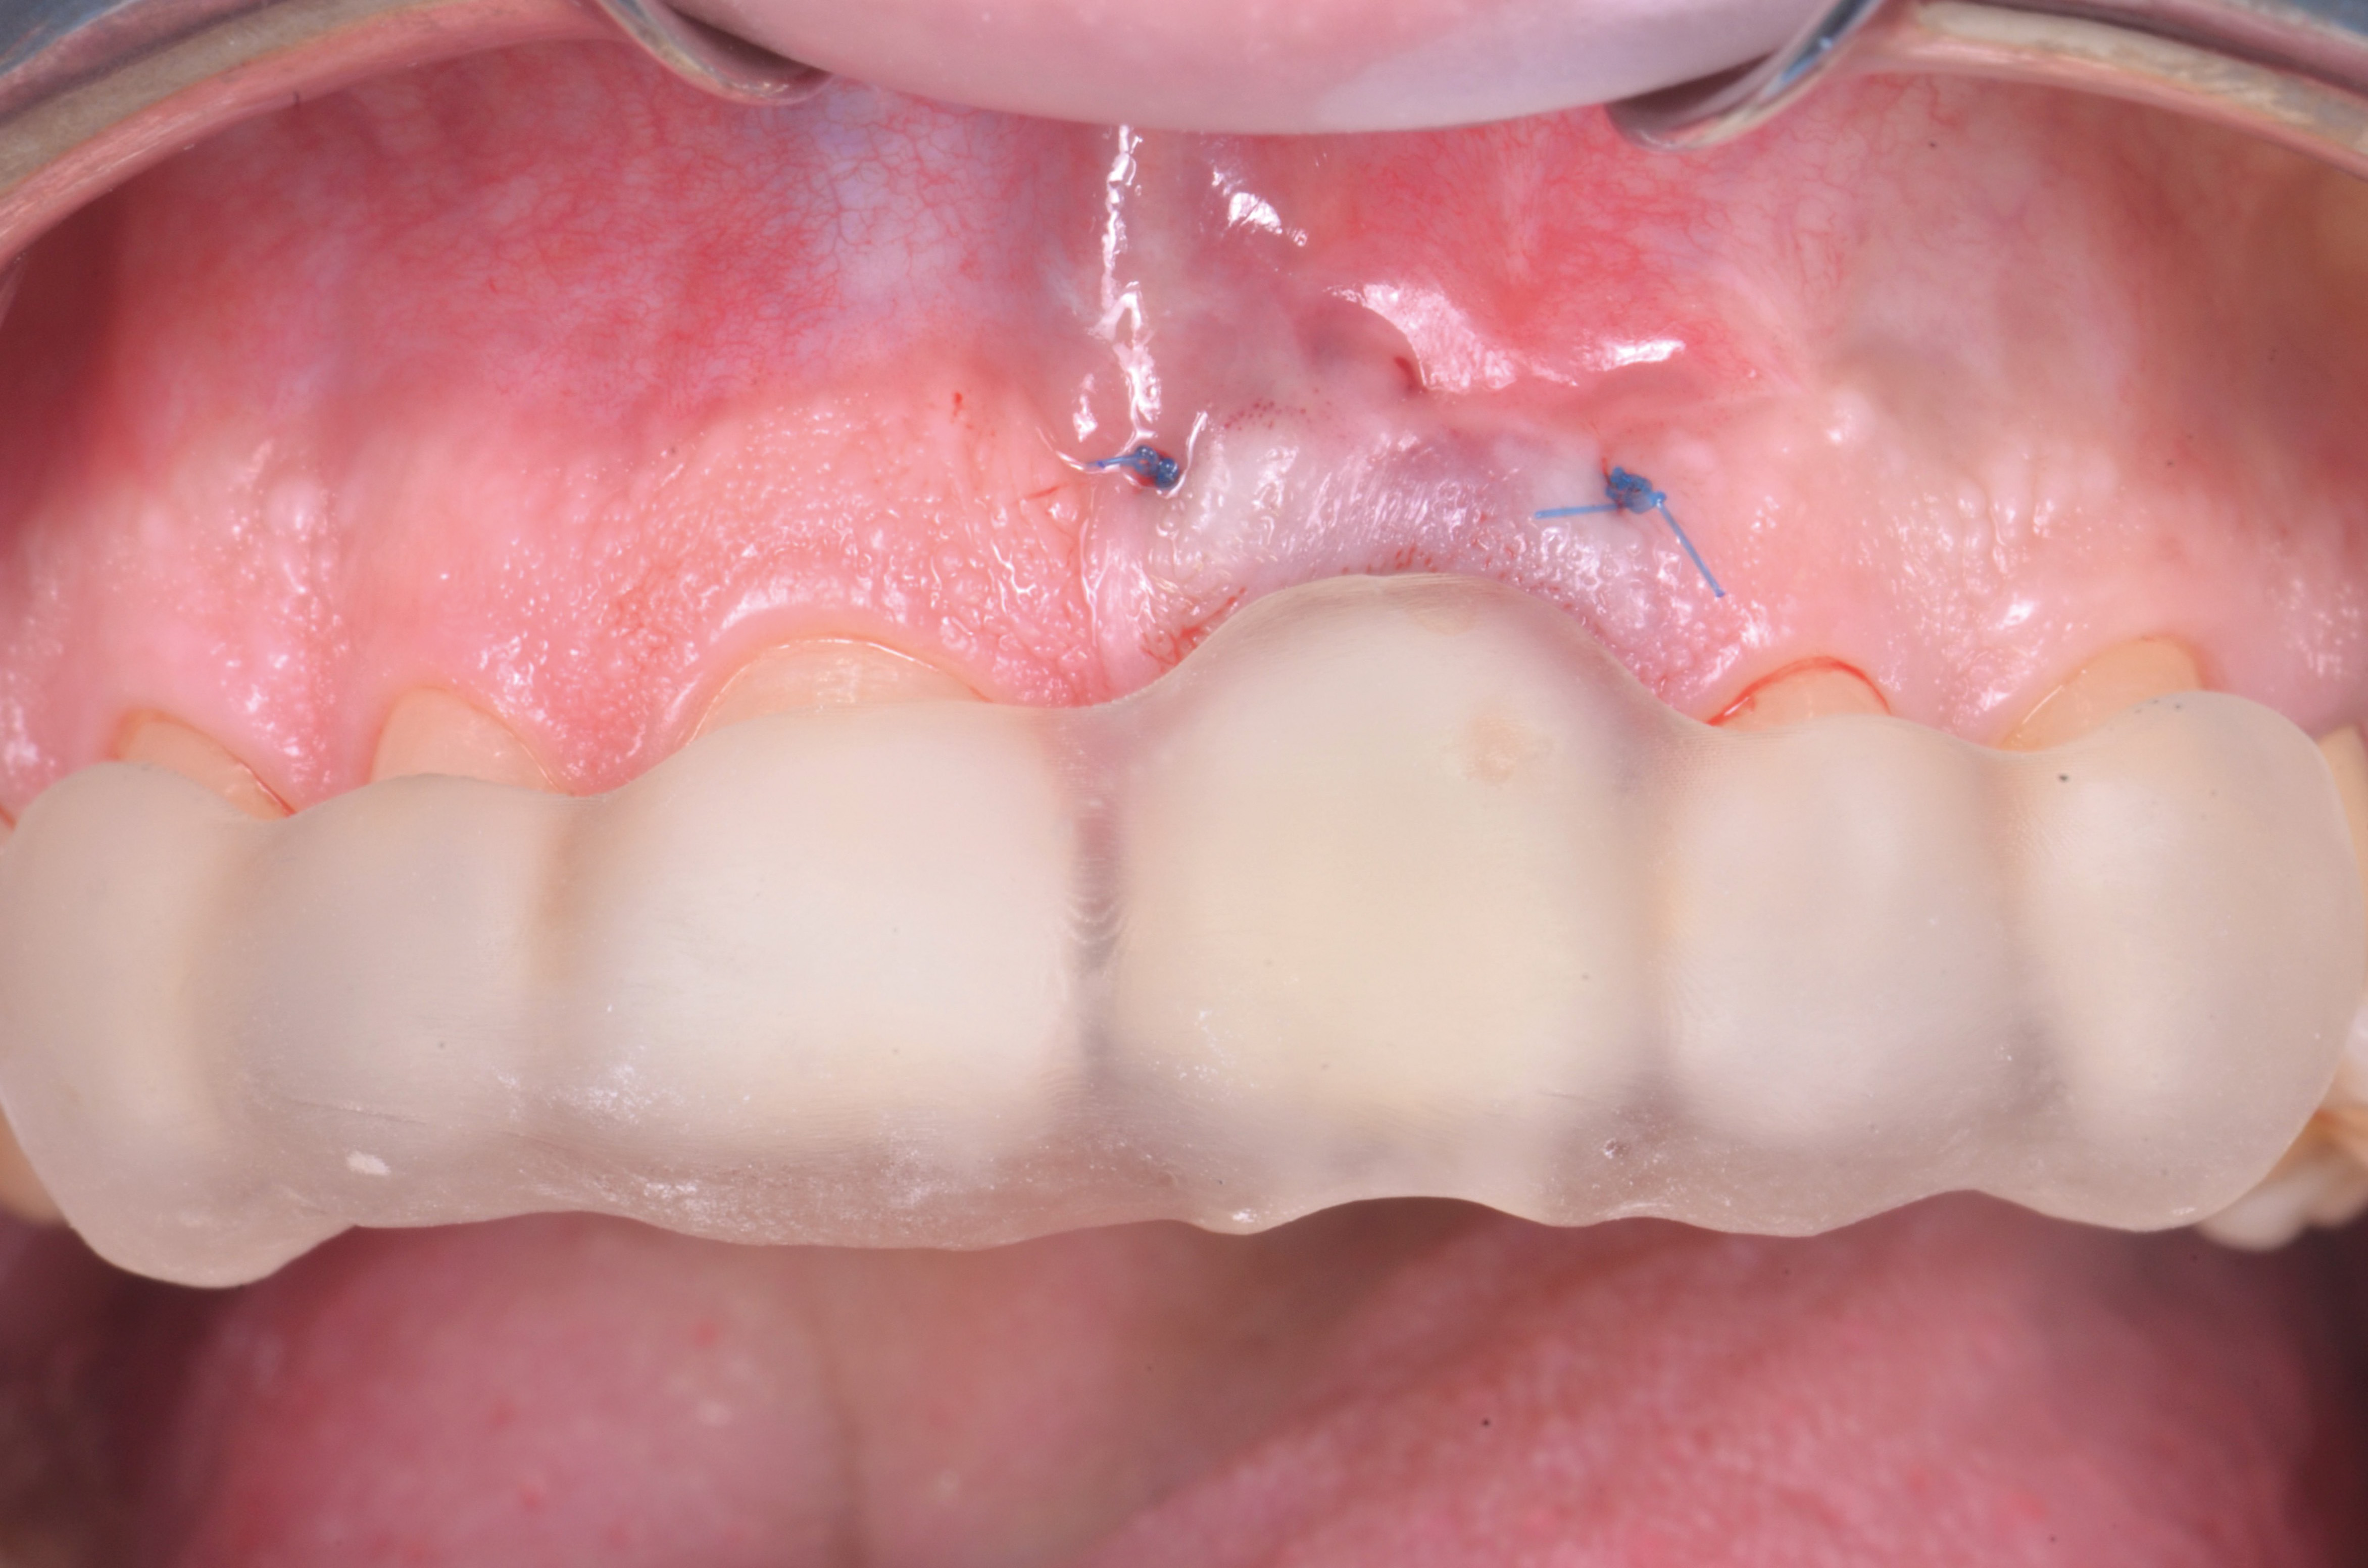

Dal momento che l’impianto presentava un torque di inserimento superiore ai 40 N/cm2 è stato possibile proseguire con il trattamento come da progetto con la protesizzazione immediata. L’elemento provvisorio è stato fissato con del composito fluido al pilastro provvisorio grazie al posizionatore stampato 3D che ha permesso di mantenere l’esatta posizione progettata a software (fig.12).

A questo punto, il provvisorio è stato rimosso e rifinito in modo da creare un profilo di emergenza che sostenesse il tessuto innestato e poi consegnato (fig.13, 14).